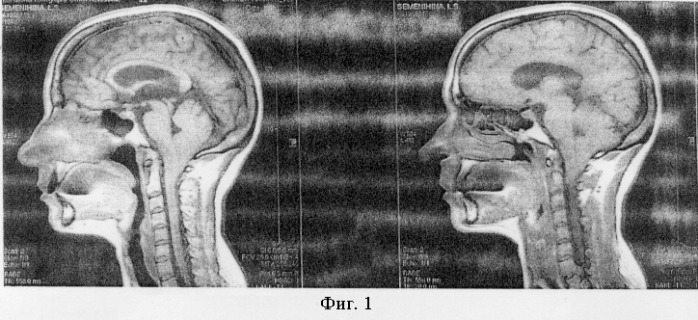

Аномалия Арнольда-Киари: MRI снимки